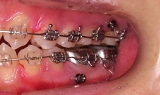

CASE1

前歯の歯並びが悪いのが一番気になります。

右側では良く噛めません↓(16歳/女性)

概要・担当医コメント:叢生・右側咀嚼障害↑

マルチブラケット装置/動的治療期間26ヶ月(23回)

/費用概算:60万円

高校の部活も矯正も両方頑張れたそうです。

上顎右側の小臼歯を1本のみ抜歯させていただき,あとは上下の歯列アーチ形態の修正にて矯正できました。